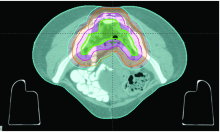

| [39] | Cella L, Ciscognetti N, Martin G, et al. Preoperative radiation treatment for rectal cancer: comparison of target coverage and small bowel NTCP in conventional vs. 3D-conformal planning.[J]. Med Dosim, 2009, 34(1):75-81. DOI: 10.1016/j.meddos.2008.04.001. doi:10.1016/j.meddos.2008.04.001 |

| [42] | 中国医师协会结直肠肿瘤专委会放疗专委会, 中华医学会放射肿瘤治疗学分会, 唐源, 等. 直肠癌术前/术后适形/调强放疗靶区勾画共识与图谱[J]. 中华放射肿瘤学杂志, 2018, 27(3):227-234. DOI: 10.3760/cma.j.issn.1004-4221.2018.03.001. |